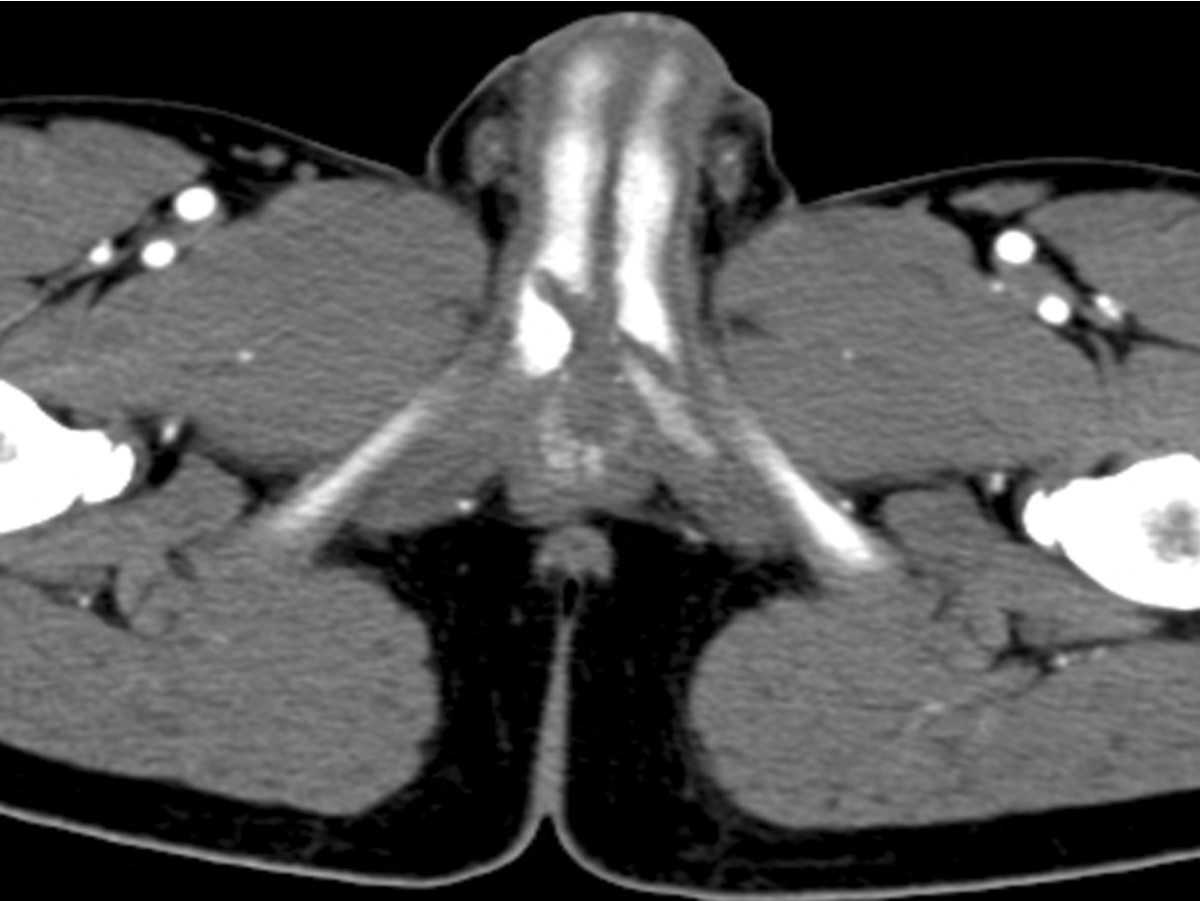

지속발기증(priapism)이 있어 CT를 촬영하였고 구부요도 (bulbous urethra) 부위의 양쪽 음경해면체에 사선모양으로 연결되는 선 모양의 낮은 감쇄 병변이 보여 양측 음경해면체의 파열(bilateral corpus cavernosal rupture)을 의심하였다(Fig. 2).

Fig. 2.

Fig. 2. Axial image with contrast enhanced CT scan following cystostomy demonstrates linear low density lesion penetrating both corpus cavenosum at the bulbous urethral level of proximal penis.